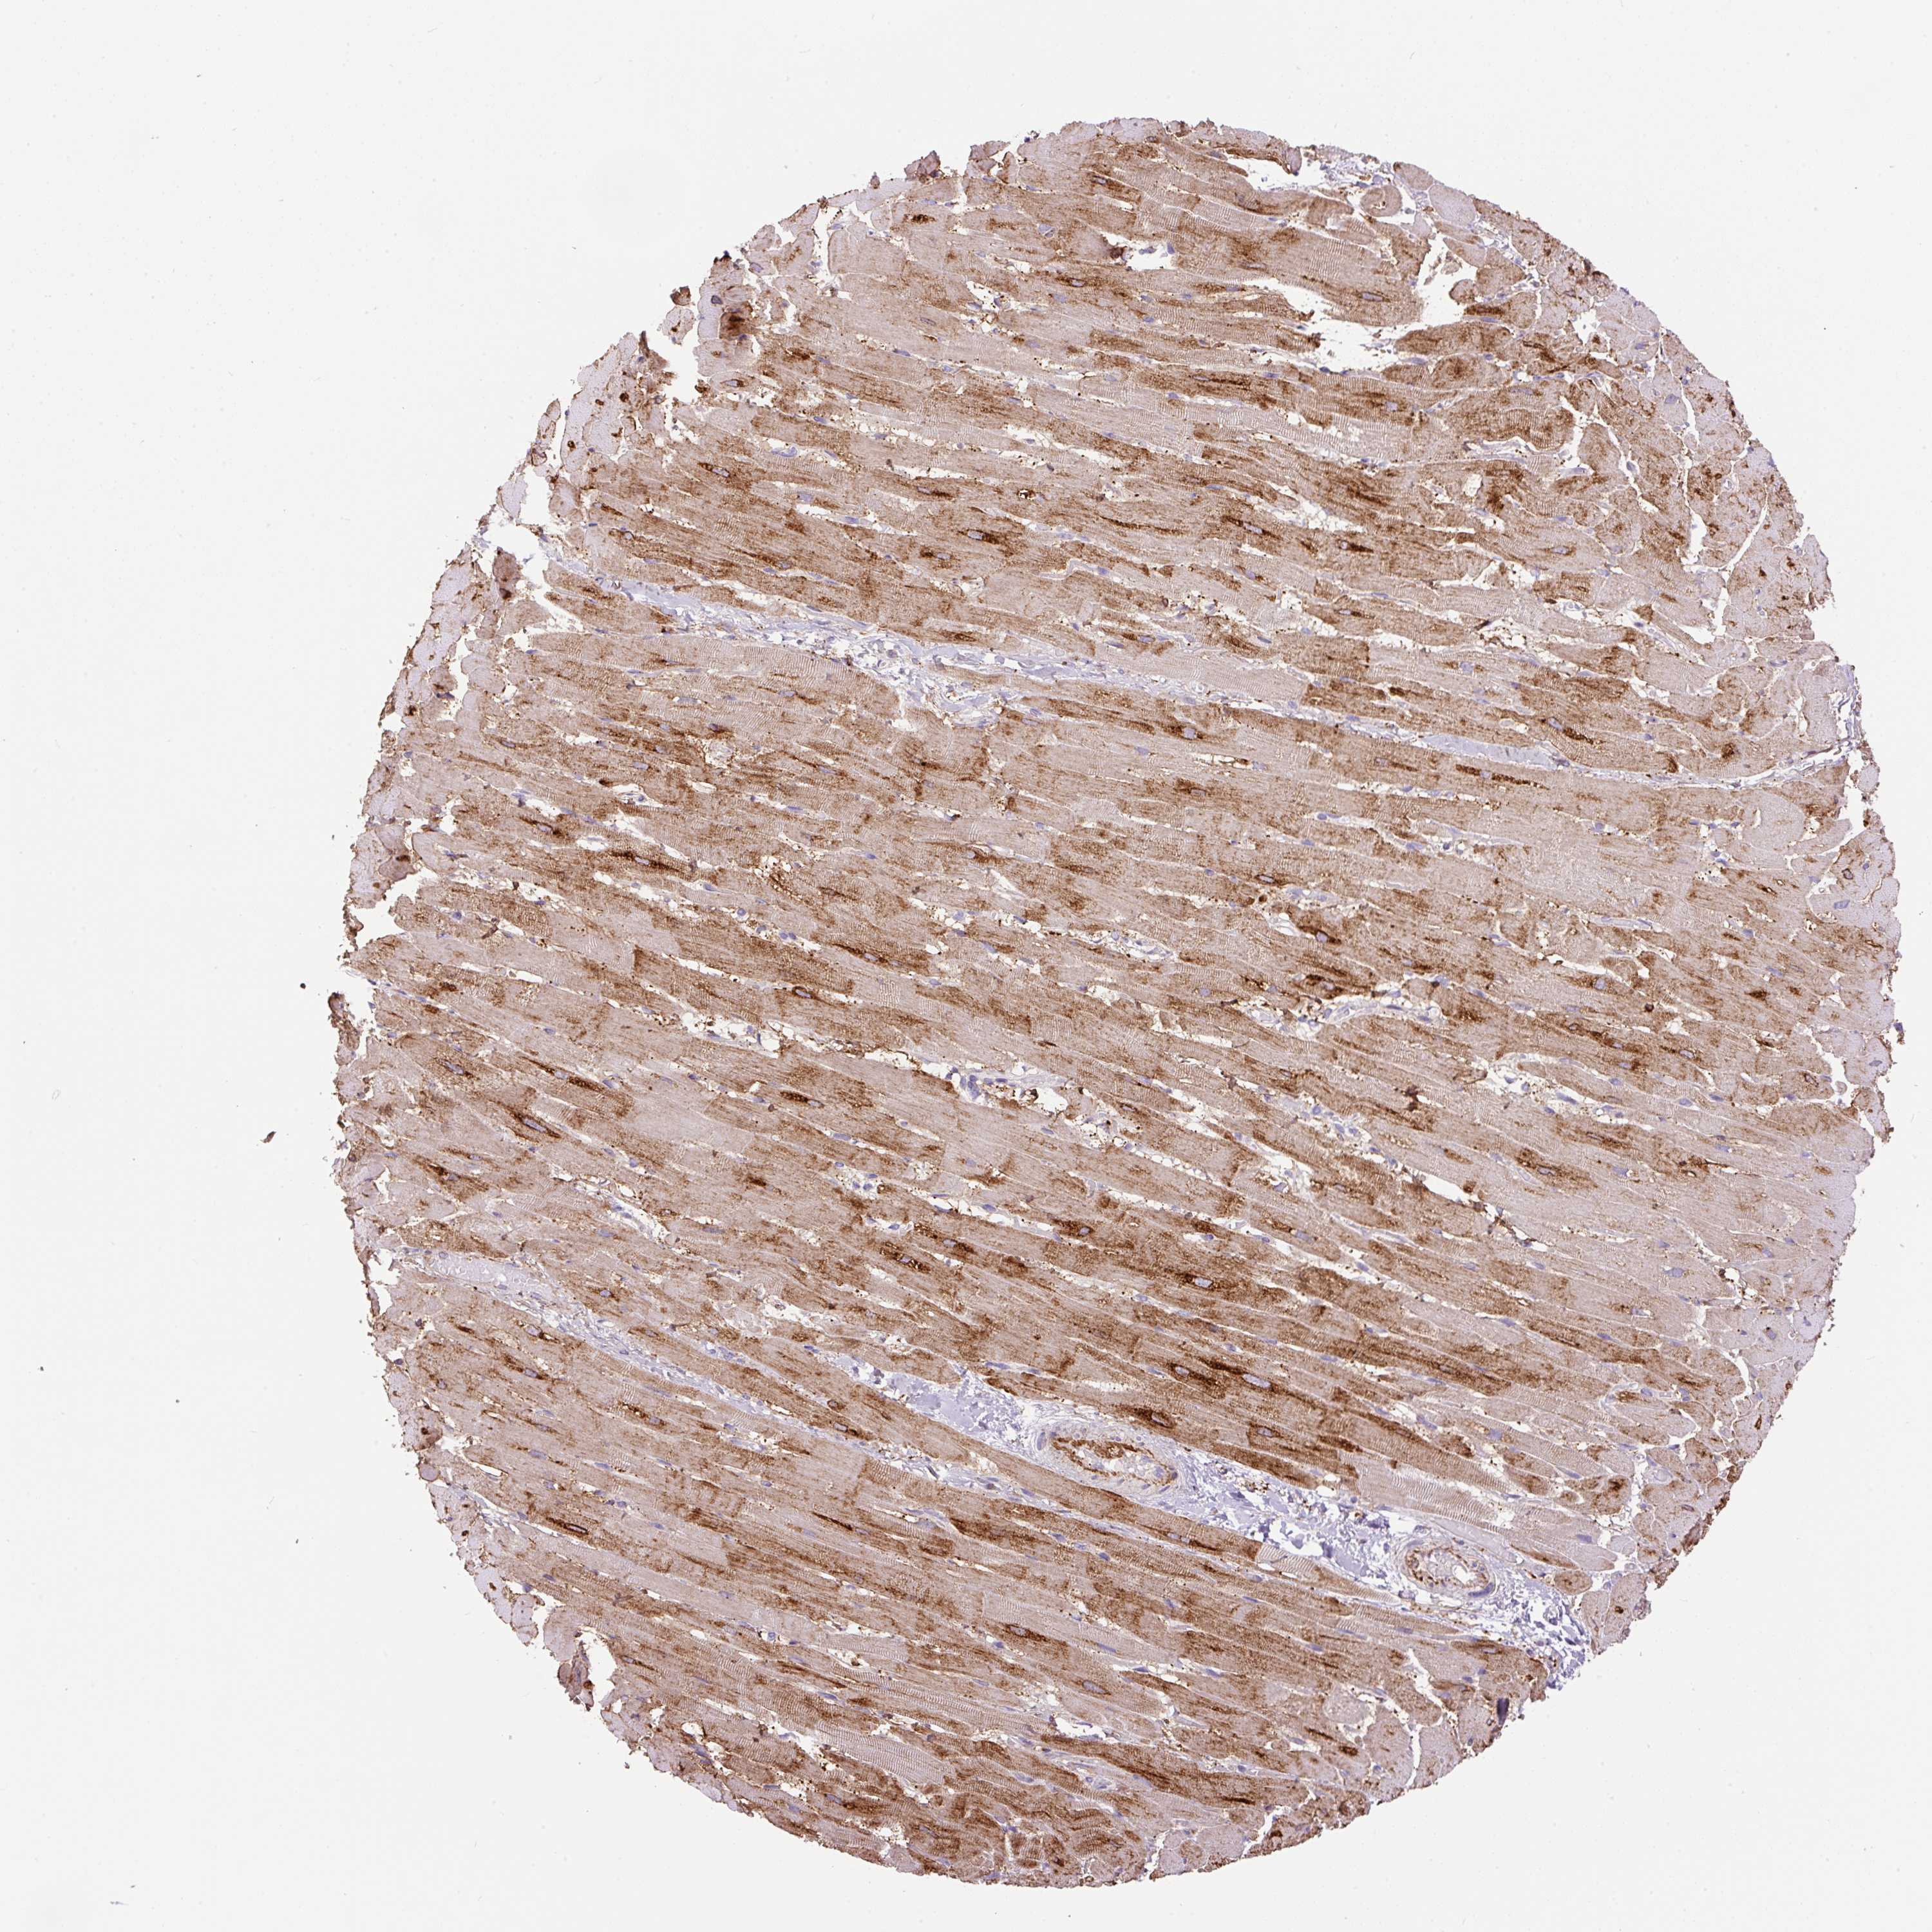

HEART MUSCLE - Antibody stainingi

Antibody staining in the annotated cell types in the current human tissue is reported as not detected, low, medium, or high, based on conventional immunohistochemistry profiling in selected tissues. This score is based on the combination of the staining intensity and fraction of stained cells.

Each image is clickable and will lead to virtual microscopy that enables deeper exploration of all samples and also displays staining intensity scores, fraction scores and subcellular localization as well as patient and tissue information for each sample.

Antibody HPA043900Antibody CAB004541

Cardiomyocytes HighNot detected